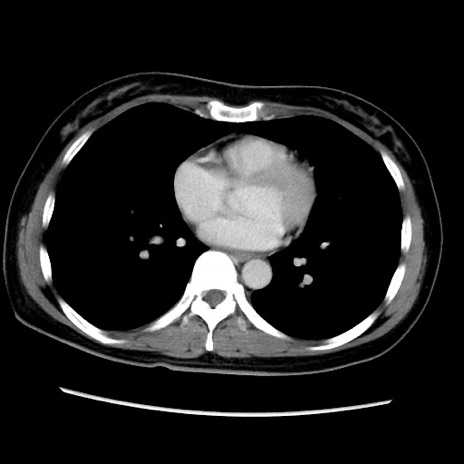

MRI(4日後)

【症例】40歳代女性

【主訴】上下腹部痛

【現病歴】2日目から下腹部痛あり。夜間は痛みで眠れなかった。昨日より上腹部痛と下痢が出現。臥位で痛みは軽快したため、休んでいた。本日になって臥位でも立位でも痛みが強くなってきたため救急要請。

【既往歴】子宮内膜症

【身体所見】部:平坦・軟、左上下腹部に圧痛あり、反跳痛あり。

【データ】WBC 21800、CRP 26.78